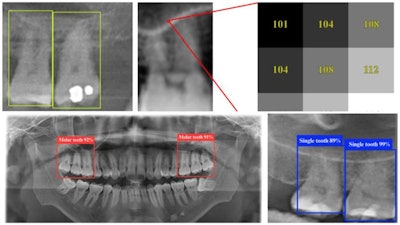

For this study, researchers trained deep-learning models using dental panoramic radiograph (DPR) images, enabling them to detect key anatomical features. YOLO (You Only Look Once) is an object-detection algorithm recognized for its speed and precision, according to the story.

The YOLO 11n variant is specially optimized for medical imaging, allowing it to identify teeth and sinus structures in a single scan with high accuracy. Unlike traditional approaches that require multiple steps and expert interpretation, YOLO 11n processes images in real time, quickly pinpointing affected areas.

Sample dental panoramic radiographs as seen by the YOLO 11n deep learning model, which can identify tooth structures with up to 98.2% accuracy. Image and caption courtesy of Pei-Yi Wu et al. Licensed under CC BY-NC-ND.